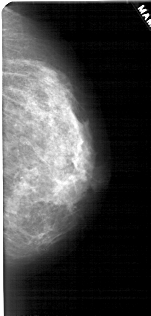

A_1790_1.LEFT_MLO

LEFT_MLO LINES 5446 PIXELS_PER_LINE 2521 BITS_PER_PIXEL 12 RESOLUTION 43.5 OVERLAY